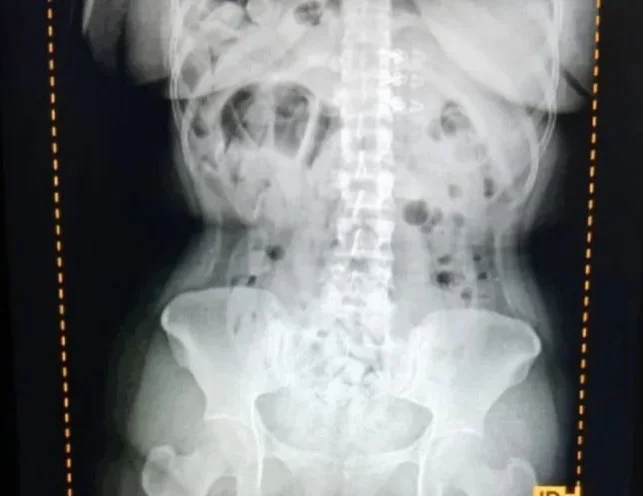

Durante un control de rutina al vehículo, los gendarmes advirtieron que tres pasajeras manifestaban molestias abdominales, lo que despertó sospechas sobre un posible hecho ilícito. Ante esta situación, fueron trasladadas al Hospital de Trancas, donde se les practicaron estudios radiográficos que permitieron detectar la presencia de cápsulas en sus estómagos.

Debido al riesgo que este tipo de modalidad representa para la salud, las mujeres fueron derivadas al Centro de Salud Zenón Santillán, en San Miguel de Tucumán, donde evacuaron un total de 198 cápsulas.

Los envoltorios fueron sometidos a la prueba de campo Narcotest, que arrojó resultado positivo para cocaína, con un peso total de 2 kilos con 328 gramos.